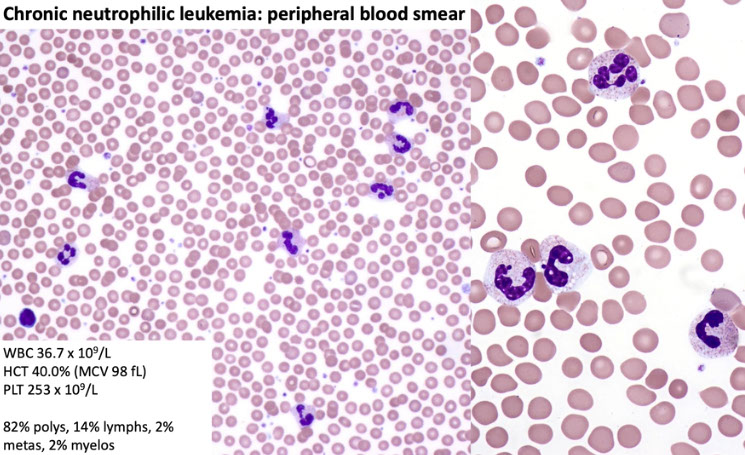

Chronic Neutrophilic Leukemia (CNL)

Rare, in older males, always in PB and BM, usually infilatrates liver and spleen

Persistent leukocytosis without a left shift (100 X 109/L).

- Toxic granulation and Döhle bodies are present.

- Rare NRBC can be seen.

- Elevated LAP.

BM marked cellularity.

Neutrophilic hyperplasia.

No evidence of myelodysplasia.

Negative for Ph1 chromosome.

Neutrophils often appear toxic with coarse granules

1.) WBC > 25,000 (in PB), with majority (>80%) neutrophils + bands, and <10% immature myelocytes (pro-,myelo-,metamyelo-), <1% blasts